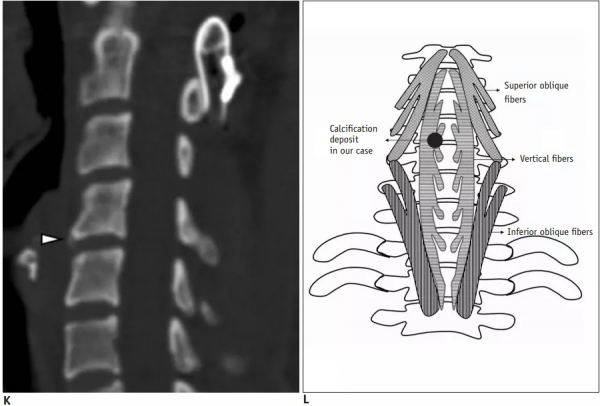

30歲女性,診斷為頸長肌鈣化性肌腱炎,但鈣化位於不尋常的位置:C4-5椎間隙前側。A:頸椎側位片示寰樞椎半脫位(長箭頭)和椎前軟組織腫脹(無線箭頭);B,C和D:頸椎MRI示C1-6椎前軟組織腫脹伴積液,D示齒狀突骨侵蝕(無線箭頭)

上述病人,E為增強,F為抑制像,G和H:經非甾體抗炎藥治療3天后查頸椎CT示C4-5椎前無定形鈣化。

上述病人,I和J: 入院4天后複查頸椎MRI示椎前積液明顯減少; K,隨訪2個月複查CT示C4-5前鈣化灶減小。(PMID: 21852912)